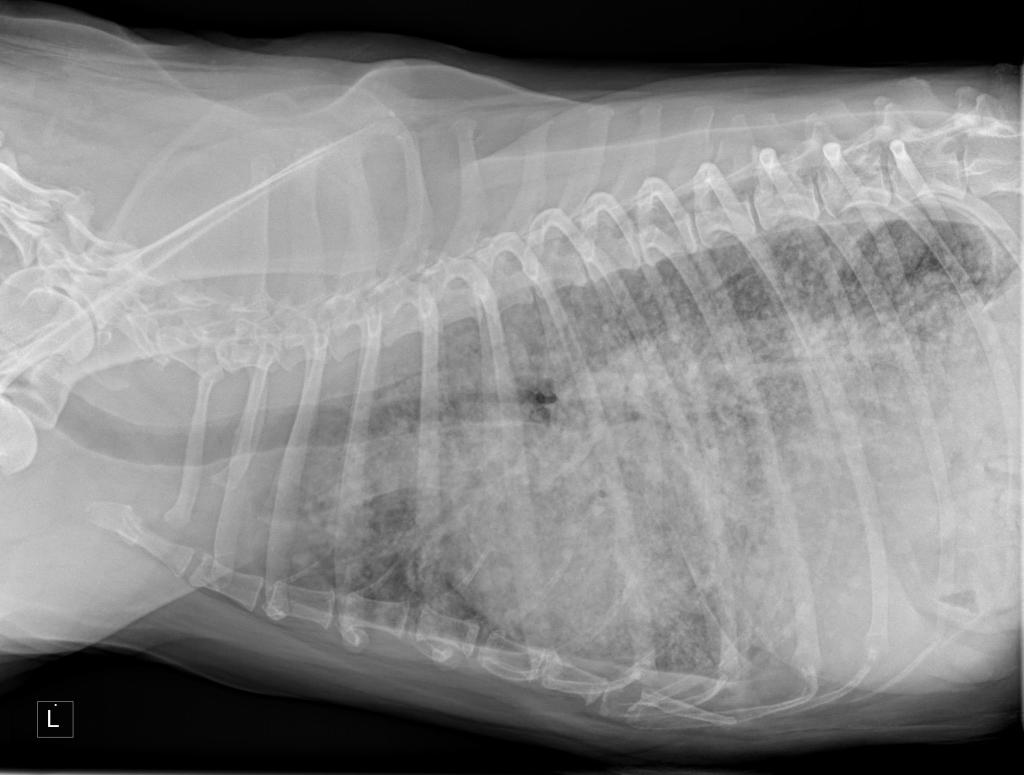

Dr. Winters recommended a further xray of Hazel’s lungs and some blood work.

But the most important indicator of it being something other than a fungal infection was that the xray showed Hazel’s lungs to be worse.

This can be more readily seen if I publish the xray image of yesterday and the image taken on the 15th April; see below.

Despite not truly understanding these images both Jean and I quickly thought the top one, taken yesterday, showed a decline in Hazel’s lungs compared to the lower one, taken on the 15th April.

Dr. Winters couldn’t be sure without a physical examination of the lung tissue but on the balance of probability she believed Hazel was at an advanced stage of cancer with the tumor somewhere in the body and that her lungs were showing that the cancer had metastasized!